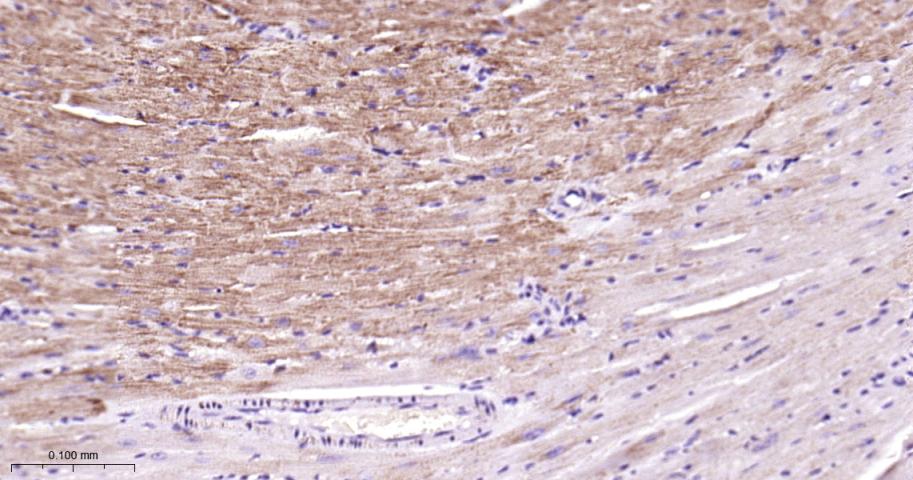

Paraformaldehyde-fixed, paraffin embedded Human Heart; Antigen retrieval by boiling in sodium citrate buffer (pH6.0) for 15 min; Antibody incubation with COX4I1 Monoclonal Antibody, Unconjugated(bsm-52750R) at 1:200 overnight at 4°C, followed by conjugation to the bs-0295G-HRP and DAB (C-0010) staining.